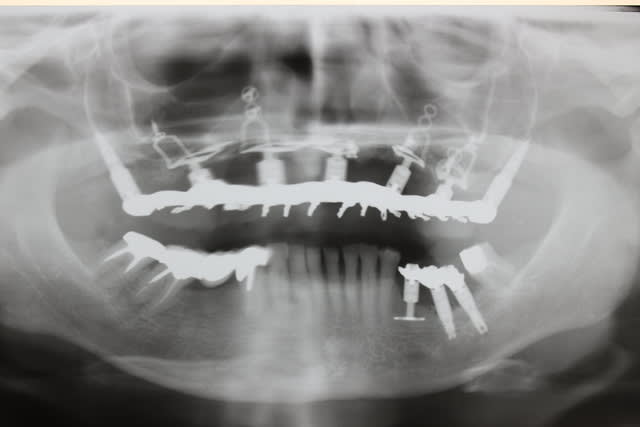

On ne dirait pas la même crête et pourtant il s agit bien de la patiente en préop et 18 mois plus tard...

Quel changement de volume et de qualité tissulaire...

qd tu vois la transformation tissulaire au niveau du volume et de la qualité des muqueuses avant-après, je doute très fort que ce soit une muqueuse diapneusique comme tu le laissais entendre...

Seuls les 2 PLM 3.5 des plaques zygomatiques ont été ôtées pour le définitif... Celles des plaques pariétales et du monodisk était pil à ras de gencive tant cela a bien proliféré

Néanmoins je n emploie plus les plaques G3 mais uniquement les G2 , ce qui est un grand progrès...

Mais j ai aussi eu des émergences pfs trop haute par rapport à l épaisseur muqueuse mais ça c était avant d employer du nanobone